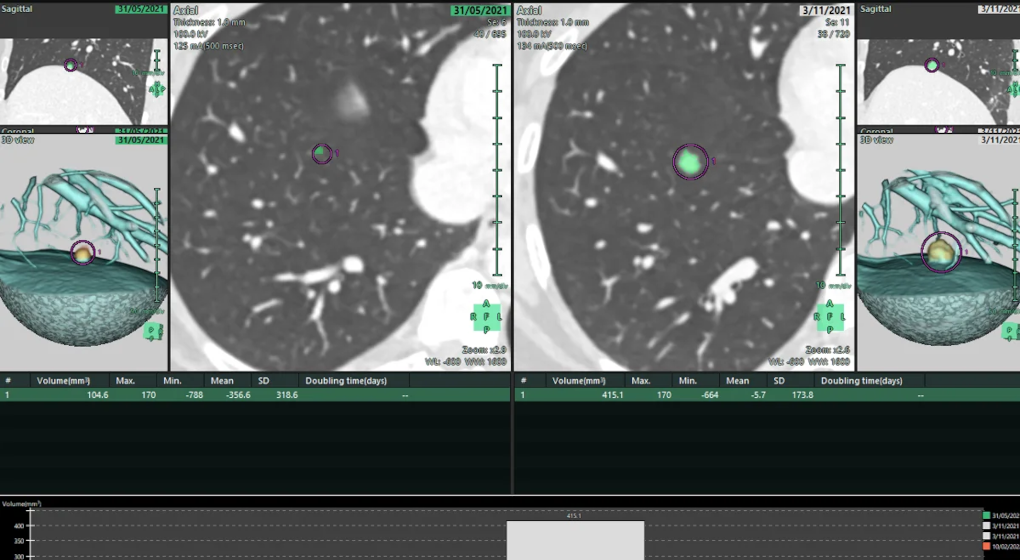

Le chirurgien ou le radiologue qui intègre les scanners thoraciques d’un patient dans le logiciel obtient rapidement une reconstruction 3D complète de tous les vaisseaux, artères et bronches des poumons.

De plus, la clinique pourra “améliorer le protocole de suivi radiologique de ses patients en montrant l’évolution de (micro)nodules et autres métastases en images 3D, et en intégrant ces images aux comptes-rendus des scanners réalisés au sein de l’institution“, indique-t-elle dans un communiqué.